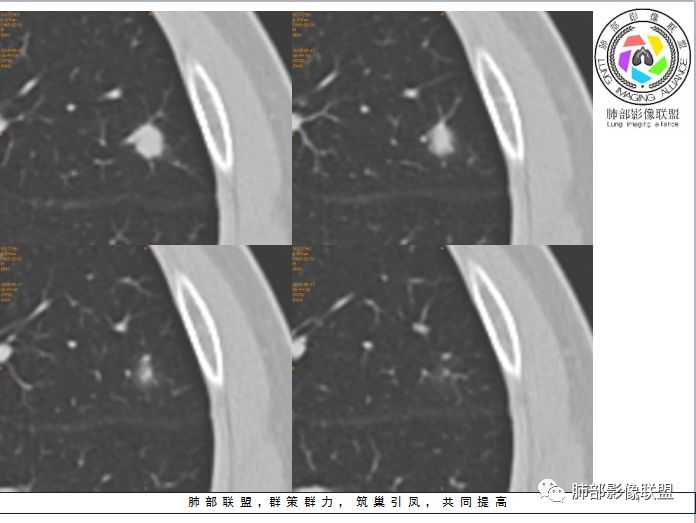

孤立结节型隐球菌影像表现:

划重点:1、胸膜下、两下肺多见。

2、“3个1/3”:1/3与胸膜相连,1/3内部可见空泡征,1/3有晕征

3、“2个2/3”:2/3与胸膜有间隙,2/3近段与血管相连。

1、与炎性假瘤、恶性肿瘤鉴别:恶性肿瘤边缘膨隆,收缩也是毛毛糙糙的,炎性假瘤收缩力较强,边缘凹陷的多。隐球菌孤立结节收缩力弱,膨胀力也弱,与胸膜关系多为糊墙,部分有间隙。右边两幅可以看到胸膜增厚,胸膜下脂肪间隙增宽。晕中长毛刺,边缘平直,血管走行自然,鉴别肺癌。